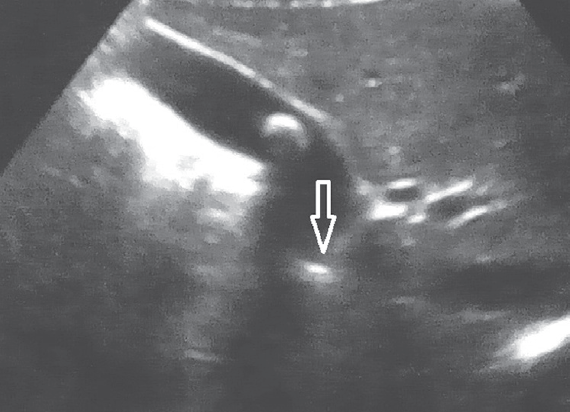

Результаты исследования. У всех пациентов с желчнокаменной болезнью выявлены различные варианты деформации в области пузырного протока. Одной из основных причин возникновения желчнокаменной болезни у детей являются изменения в области пузырного протока. Ни у одного пациента не было найдено конкрементов во внепеченочных желчных ходах. У пациентов с хроническим бескаменным холециститом патологии в области пузырного протока найдено не было.

Заключение. Одной из основных причин возникновения желчнокаменной болезни у детей являются изменения в области пузырного протока, что вероятнее всего приводит к затруднению оттока желчи из желчного пузыря, с последующим образованием конкрементов. Следовательно, проведение консервативного лечения при желчнокаменной болезни у детей представляется малоэффективным и методом выбора при лечении данной патологии может быть холецистэктомия.